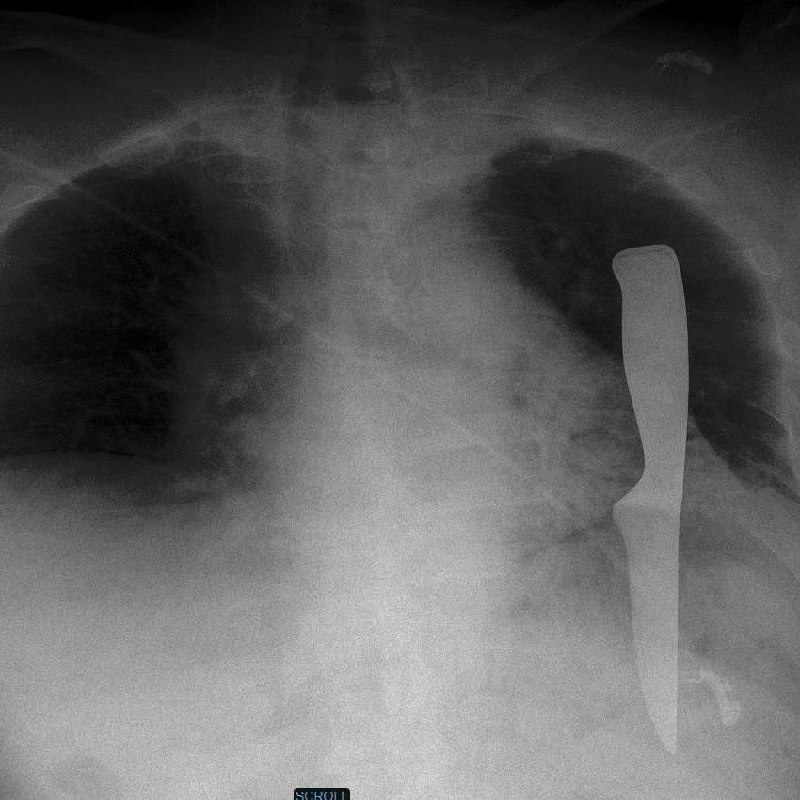

👉🏻 В Городская клиническая больница № 1 им. Н. И. Пирогова поступил мужчина с множественными колото-резаными ранениями груди, шеи и предплечья. Во время обследования врачи обнаружили в левой плевральной полости… кухонный нож.

«Мы не поверили своим глазам. Со столь необычной клинической ситуацией мы не сталкивались», — рассказал дежурный хирург Сулим Давлетгириев.

👩‍⚕️ Пациента немедленно доставили в операционную. Хирурги извлекли нож и ушили повреждённое в шести местах лёгкое. Позже выяснилось: лезвие остановилось буквально в нескольких миллиметрах от сердца, не повредив его оболочки.

Операцию проводила мультидисциплинарная бригада — хирурги, травматолог, реаниматологи. Работа — ювелирная, риск — колоссальный.